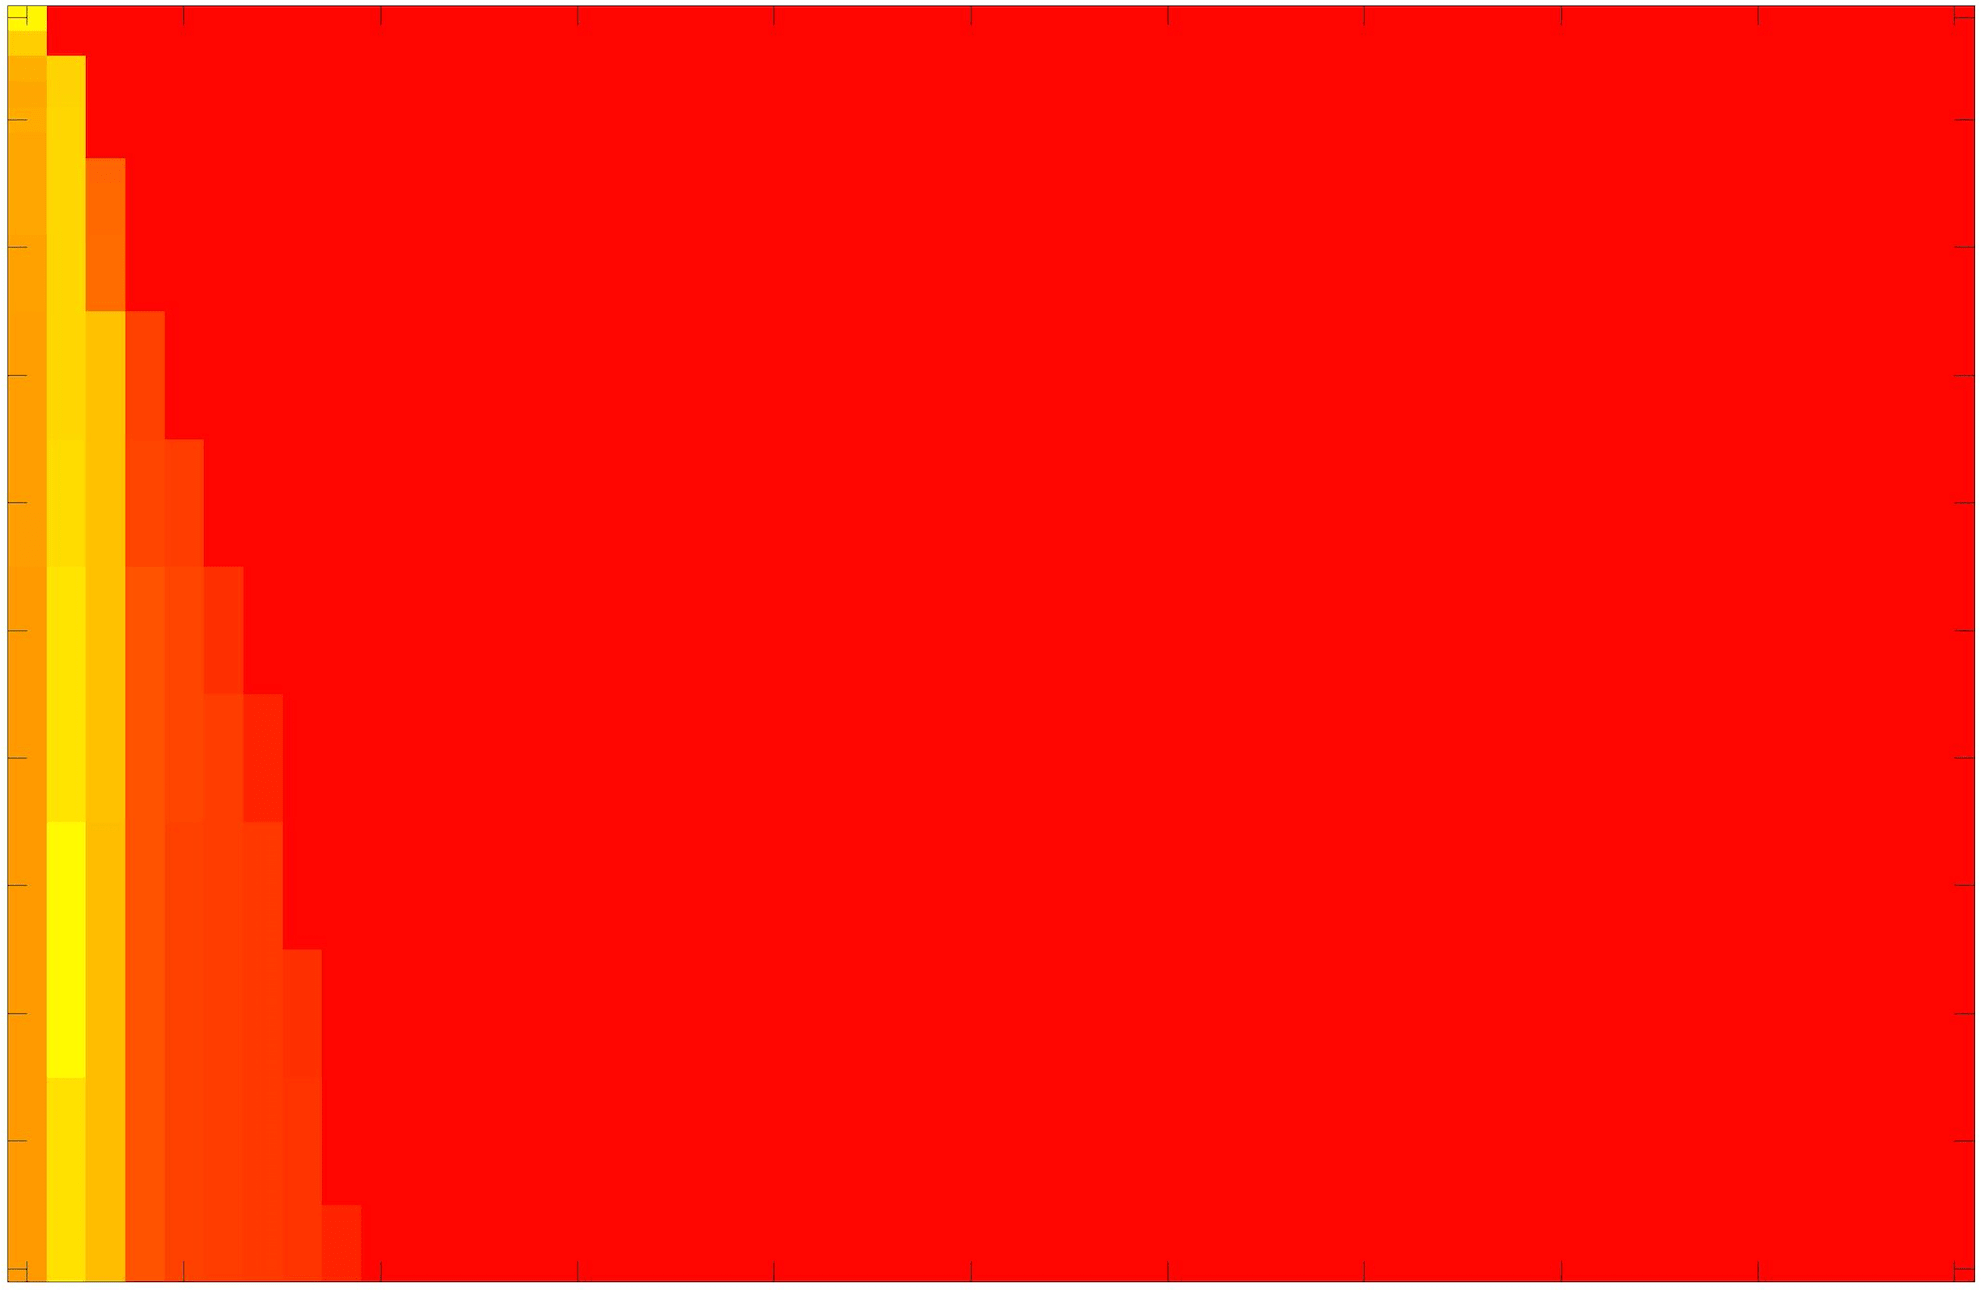

where refers to the number of points in the enclosed region. This takes values in the range , with higher TC values indicating a more accurate segmentation. In the following we will represent accuracy visually from red () to green (), with the intermediate scaling of colours used shown in Fig. 8. This will be particularly relevant in §7.2.

The TC values for the parameter sets are presented as heatmaps in Figs. 11–13. A heatmap is a convenient way to display accuracy results for hundreds of tests concisely. In Fig. 9 we give an example heatmap with the same axes used for those in Figs. 11–13. For each of the combinations of parameter values we give the TC value of the segmentation result and represent it by the appropriate colour. The corresponding colour scale is shown in Fig. 8. Qualitatively, the more green areas of the heatmap the more accurate the model is for a wider set of parameters. Example results for Test Image 5 when varying (with ) for the proposed model are given in Fig. 10. Here it can be seen what each accuracy result corresponds to visually.

Note. The axes have been removed from the heatmaps in Figs. 11–13 for presentational clarity. However, to be explicit, the axes used in all heatmaps are the same as those in Fig. 9.

Synthetic Images. These results are presented in Fig. 11. For Test Images 1–2 we see poor parameter robustness from all competing models, except for GAV which performs reasonably well. However, the proposed model has minimal parameter sensitivity for these images, with good results achieved for almost every combination of values tested. For Test Image 3 all models have a reasonable parameter range (except for RSF), however the proposed model gives better quality results for a wider parameter range. The other models achieve reasonable results here as the foreground intensity of the ground truth is greater than the background , whereas for Test Images 1–2 they are equal . These results highlight the key advantage of the proposed model.

Real Images. In Fig 12 we present results for Test Images 4–6. Here, the proposed model performs in a similar way to its competitors because these images are more typical selective segmentation problems in the sense that there is a clear distinction between the foreground and background intensities. In particular, the values in each case are: Test Image 4 , Test Image 5 , and Test Image 6 . It can be seen that the proposed model is competitive compared to previous approaches. The performance is quite poor for Test Image 5, but is arguably still the best for this challenging case. In Fig. 13 we present results for Test Images 7–9. Here the proposed model outperforms previous approaches significantly for each image. This is mainly due to the type of image considered. Specifically, the true intensities are: Test Image 7 , Test Image 8 , and Test Image 9 . The proposed model is capable of achieving results where , with other models failing completely in these cases.